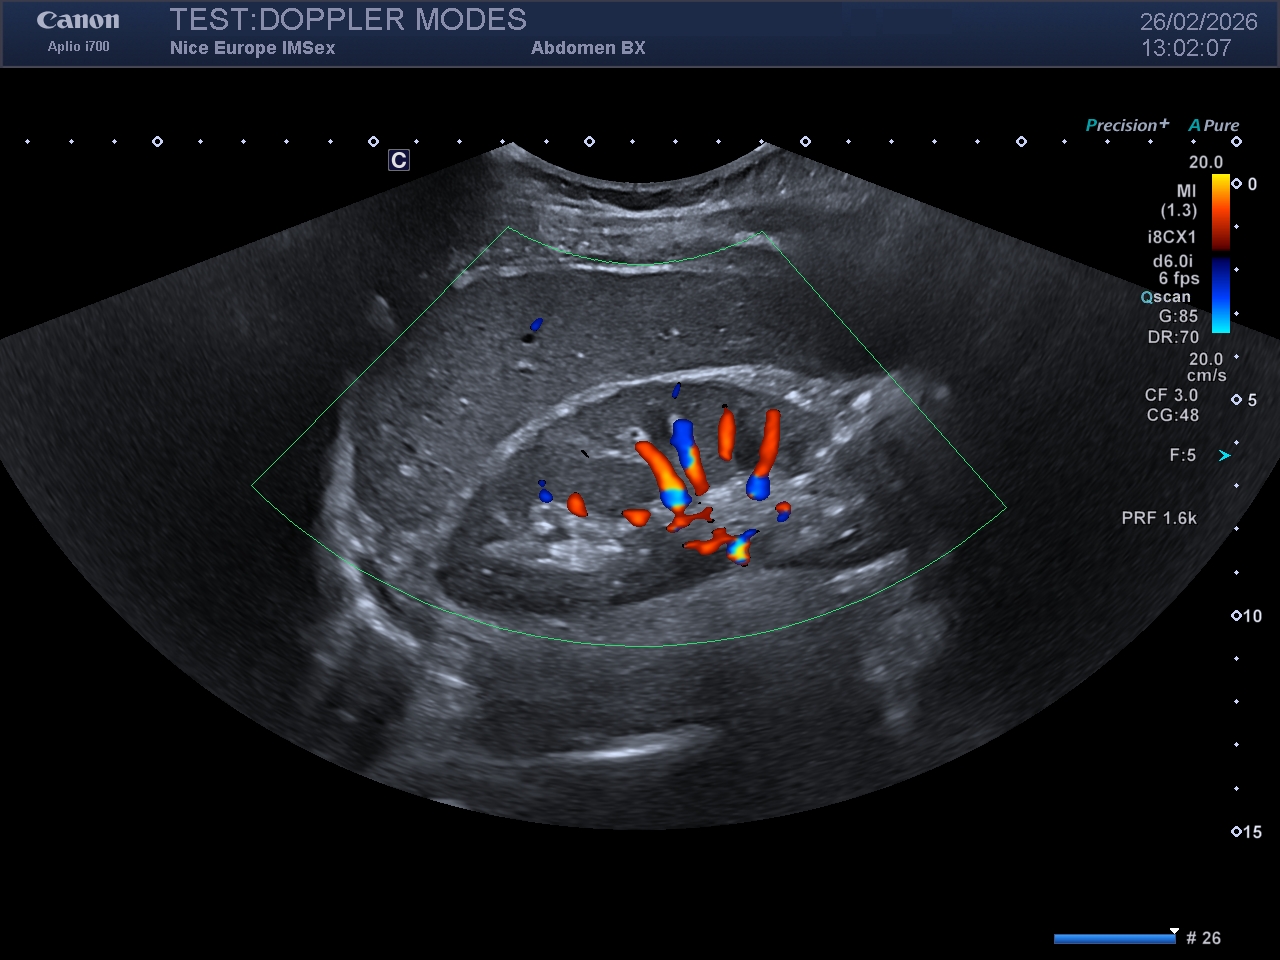

Le Doppler couleur est conçu pour cartographier la vitesse moyenne et la direction du flux sanguin. Il traduit ces informations en une carte de couleur qui se superposera à l'image échographique "mode B" (en nuances de gris).

Sur un réglage dit "usine", ou par défaut :

- le flux rouge se rapproche de la sonde

- le flux bleu s'éloigne de la sonde

Ce mode est idéal pour évaluer les directions et les vitesses relatives de circulation des flux. Il est par contre très peu utile pour les fluxs lents, en raison de filtres empêchant leur visualisation et est très dépendant à de nombreux réglages (cf ci après, section Professeur), notamment un point crucial et capital : l'effet Doppler est nul, donc non mesurable, lorsque l'angle d'observation est de 90°.

Légende : Image en Doppler couleur d'un rein droit